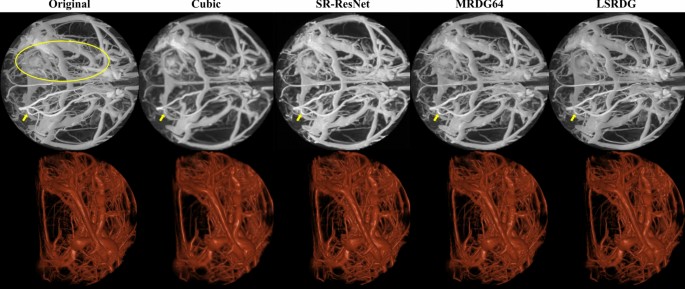

In addition, the proposed model trained without and with GAN also performed better on stroke data compared to others and generated a very similar image to the original HR image, as shown in Figs. 6 and 7, respectively. For further comparison, Supplementary Figs. 1 and 2 as well as Supplementary Animations 1 and 2 show generated images using PSNR-oriented models and PSNR and GAN–oriented models on HC data, respectively. In addition, Supplementary Figs. 3 and 4 as well as Supplementary Animation 3 also show a visual comparison of different models trained on HC data and applied to stroke data. In general, compared with the cubic spline interpolation, all deep learning models performed significantly better on both HC and stroke data.

Testing PSNR-oriented models on stroke data. The first row shows the HR and LR along with the SR data generated using PSNR-oriented models after maximum intensity projection in the sagittal direction. The second row shows volume-rendered data. The yellow ellipse on the original image shows the region of infarction due to ischemic stroke, and the yellow arrows show the visual difference of the vessel in the contralateral hemisphere, which appears occluded in the LR image.